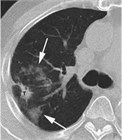

1. 放射線照射開始後早期に発症した放射線肺臓炎は重症化しやすい。

1. 放射線治療によって器質化肺炎(OP、BOOP)が起こることがある。

1. 高精度放射線治療においても放射線肺炎の発症頻度は低くはない。